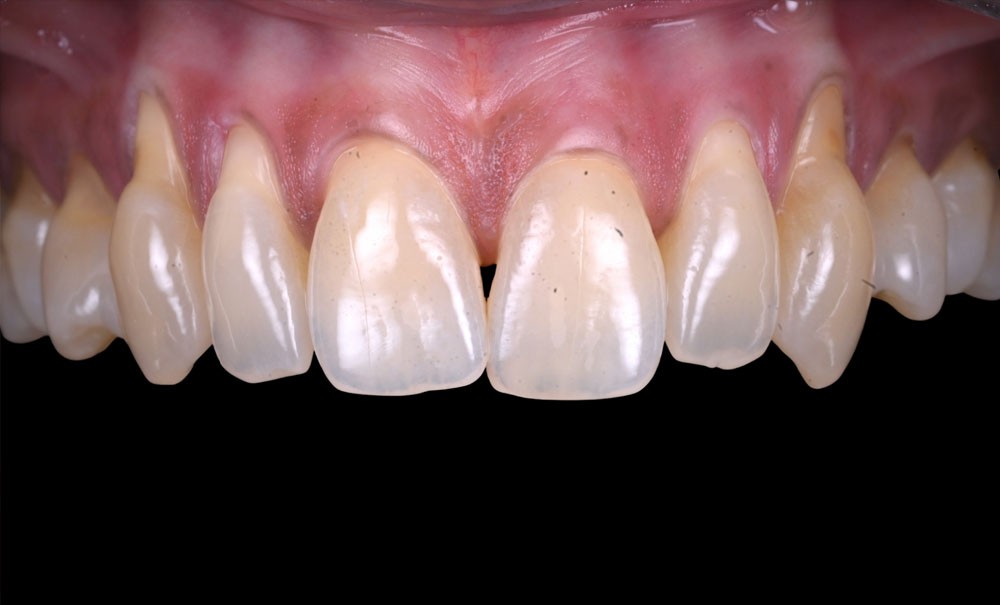

L’examen clinique révèle des récessions gingivales généralisées au maxillaire (fig. 1), de type RT1 et RT2 selon Cairo, responsables d’une hypersensibilité dentinaire marquée.